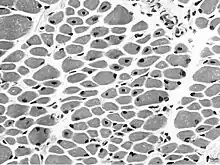

| Muscle biopsy from the quadriceps taken at 3 months of age from a girl with X-linked centronuclear ("myotubular") myopathy due to a mutation in the myotubularin (MTM1) gene and extremely skewed X-inactivation (H&E stain, transverse section). Note marked variability in fibre size, moderate increase in connective tissue and numerous central nuclei. | |

On examination of muscle biopsy material, the nuclear material is located predominantly in the center of the muscle cells, and is described as having any "myotubular" or "centronuclear" appearance. In terms of describing the muscle biopsy itself, "myotubular" or "centronuclear" are almost synonymous, and both terms point to the similar cellular-appearance among MTM and CNM. Thus, pathologists and treating physicians use those terms almost interchangeably, although researchers and clinicians are increasingly distinguishing between those phrases.

In general, a clinical myopathy and a muscle biopsy showing a centronuclear (nucleus in the center of the muscle cell) appearance would indicate a centronuclear myopathy (CNM). The most commonly diagnosed CNM is myotubular myopathy (MTM). However, muscle biopsy analysis alone cannot reliably distinguish myotubular myopathy from other forms of centronuclear myopathies, and thus genetic testing is required. Diagnostic workup is often coordinated by a treating neurologist. In the United States, care is often coordinated through clinics affiliated with the Muscular Dystrophy Association.